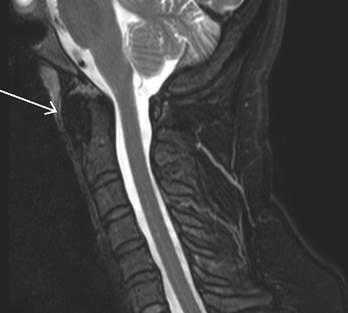

На мр-томограммах выявлялась расщелина (незаращение) передней дужки атланта, определялись особенности анатомического строения и особенности контуров передней дужки атланта в каждой из стандартных проекций (рис. 2).

Рис. 2. Коронарный и сагиттальный срезы Т2ВИ (стрелкой указаны поверхности расщепленной передней дужки)